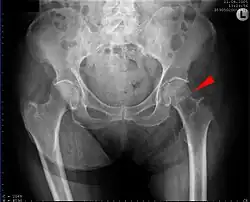

Fracture supported by dynamic hip screw

A trochanteric fracture, below the neck of the femur, has a good chance of healing.

Closed reduction may not be satisfactory and open reduction then becomes necessary.[43] The use of open reduction has been reported as 8-13% among pertrochanteric fractures, and 52% among intertrochanteric fractures.[44] Both intertrochanteric and pertrochanteric fractures may be treated by a dynamic hip screw and plate, or an intramedullary rod.[43]

The fracture typically takes 3–6 months to heal. As it is only common in elderly, removal of the dynamic hip screw is usually not recommended to avoid unnecessary risk of second operation and the increased risk of re-fracture after implant removal. The most common cause for hip fractures in the elderly is osteoporosis; if this is the case, treatment of the osteoporosis can well reduce the risk of further fracture. Only young patients tend to consider having it removed; the implant may function as a stress riser, increasing the risk of a break if another accident occurs.